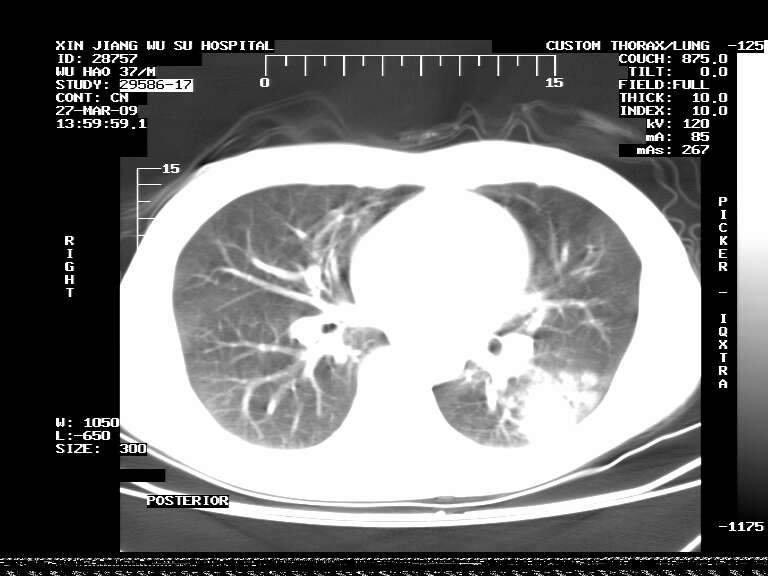

男,37岁,体检胸透发现阴影。

患者体检发现 无症状 左肺下叶占位,边缘模糊,可见血管聚束、分叶、胸膜牵拉,增强呈不均匀性强化。 首先考虑左肺下叶周围型肺癌,建议穿刺活检。

患者体检发现 无症状 左肺下叶占位,边缘模糊,可见血管聚束、分叶、胸膜牵拉,增强呈不均匀性强化。 首先考虑左肺下叶周围型肺癌,建议穿刺活检。支持!

左肺下叶见一结节病变,边缘欠清不光滑,与胸膜粘连且胸膜局限性增厚,注药后呈环形强化,动脉期壁呈明显点环状强化,静脉期壁强化减低,中心密度低无强化,灶周无明显的卫星灶和水肿区(晕征)---考虑周围性肺癌,不除外感染性病变,建议穿刺活检。

左肺下叶软组织病灶,密度较高,内见点状钙化,其周围见子灶,邻近胸膜扁平样增厚.c+病灶强化明显,中心强化弱.诊断:左肺下叶结核瘤.

周围有卫星灶,胸膜反应不明显,病灶中心有坏死。建议先抗结核治疗后,短期复查

左肺下叶大片实变影,内靠胸膜见不规则更高密度结节灶,边缘强化,相邻胸膜增厚,胸膜下脂肪线存在。考虑炎症,结核可能。